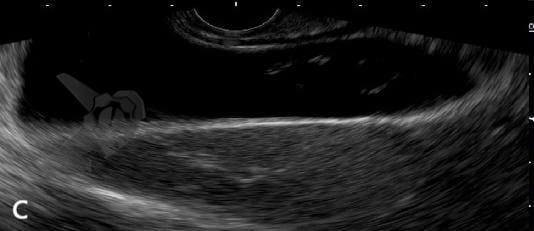

El polvo biliar se ha definido como una imagen hiperecoica flotante, sin sombra acústica posterior, observada o acentuada tras la palpación abdominal³. Se trata, por lo tanto, de la misma entidad ecográfica que, en Brasil, tradicionalmente se ha denominado “microlitiasis”, pero que no se ajusta a la definición de consenso internacional de microlitiasis y terminó siendo prácticamente ignorada por el consenso, o, en algunos casos, incluida a la fuerza bajo el término “lodo biliar”.

El polvo biliar se definió como una imagen hiperecoica flotante, sin sombra acústica posterior, observada o acentuada tras la palpación abdominal — una entidad ecográfica anteriormente denominada “microlitiasis” o “microcálculo” en nuestro medio. La introducción de este término busca conciliar los hallazgos ecográficos frecuentemente observados en la práctica diaria con las definiciones establecidas por el Consenso Internacional de 2023.